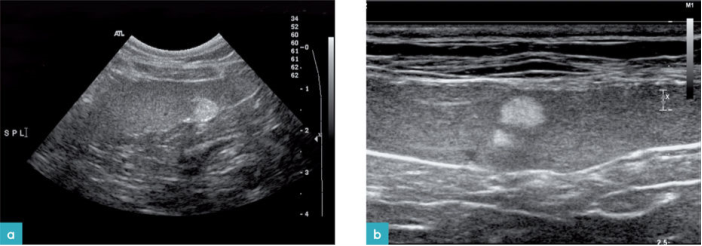

脾脏位于左侧上腹部,靠近胃底部、左肾头极与左侧腹壁(图1)。脾脏有两个表面:体壁面与脏器面。体壁面朝向左侧腹壁,表面凸起。脏器面(又称肠系膜面)朝向内侧,脾门在长轴上将脾脏分成两个部分(图2)。

脾脏含有被膜、小梁和实质组织(红髓和白髓组成)。脾脏的血管包括动脉和脾静脉,脾动脉起源于腹主动脉,脾静脉汇入到门静脉。脾动脉和脾静脉在脾门处进入脾脏,脾门位于脾脏的脏器面中间(图3.视频2)。脾门淋巴结引流脾脏的淋巴液,然后通过淋巴管注入腹腔干,最后汇入乳糜池。

健康动物的脾脏边界清晰,被膜薄而光滑(图2和图3)。脾脏的脏器面的轮廓不规则,是因为在脾门的地方有血管进出。横断面上的脾脏呈三角形(图4)。二维超声图像上很难看到脾动脉进入脾脏,需要使用彩色多普勒才能识别脾动脉(图3)。

在脾脏的脏器面,血管周围的脾脏实质内偶尔会发现高回声结节。这些结节与脂肪蓄积相关,被称为脂肪瘤或髓脂瘤(图6)。